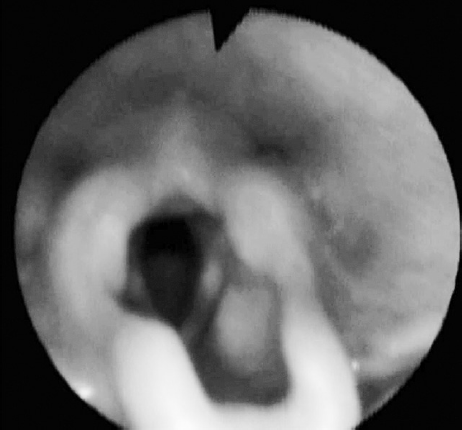

Для определения патологии гортани выполнена гибкая назофаринголарингоскопия (рис. 1).

Рис. 1. Эндофотография гортани. Врожденный порок развития гортани. Ларингомаляция 2-го типа

При назофаринголарингоскопии выявлены признаки ларингомаляции 2-го типа: надгортанник свернут в виде желоба, черпалонадгортанные складки укорочены, увеличенные черпаловидные и клиновидные хрящи выдвинуты вперед и прикрывают голосовой отдел гортани, подголосовой отдел не обозрим. Однако просвет гортани для дыхания в динамике сохранен, частичный коллапс преддверия гортани на вдохе за счет сближения краев надгортанника и пролабирования клиновидных хрящей. На рентгенограмме шеи в боковой проекции просвет подголосового отдела гортани и трахеи прослеживается на всем протяжении, не изменен (рис. 2). Кислотно-основное состояние крови — насыщение капиллярной крови кислородом 95,6 %